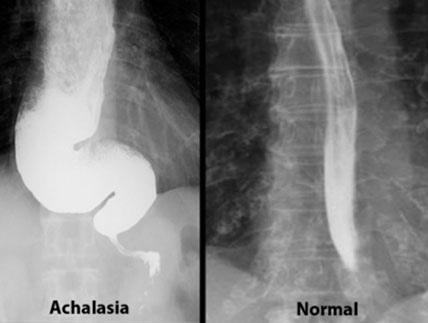

Achalasia

from Greek: A- (not); chalao (loosen / relax)

MCC Neuromuscular disorder of esophagus

inc LES tone from impaired sm muscle relaxation

Primary achalasia 2/2 degeneration of inhibitory neurons in distal esophagus

Secondary achalasia can be in Chagas, where LES fails to relax b/c destruction of myenteric (Auerbach's) plexus.

- inflam. of esophageal myenteric plexus is pathomneumonic

- damage to inhibitory (NO synthase producing) neurons

- can also be seen in DM, malig, amyloidosis, sarcoidosis, polio, surgical ablation of nerves, Down syndrome, Allgrove syndrome

Triad:

1)incomplete LES relaxation,

2) inc LES tone

3) esophageal aperistalsis

High LES opening pressure + uncoordinated peristalsis --> progressive dysphagia to solids AND liquids

- dysphagia limited to solids indicates an obstructive lesion

Primary achalasia 2/2 ganglion cell degen (inhibitory neuron degeneration, thus inc tone)

May be caused by Chaga's dz./ Scleroderma (CREST syndrome), diabetic neuropathy, or amyloidosis

Generally, worsening dysphagia to solids and liquids indicates motility disorders --> achalasia, MG, stroke, CREST syndrome

Dx: Manometry studies. Barium swallow shows "bird's beak" (stenosis of distal esophagus).

- manometry findings: 1) Aperistalsis; 2) dec LES relaxation after swallowing; 3) inc LES resting tone

Tx: 1) Pneumatic balloon dilation (may cause rupture)

2) Botulinum toxin injection to LES

3) Esophagotomy

Px: small (1/20) risk of esophageal SCC

- thus pt should get bx more frequently (annually?)